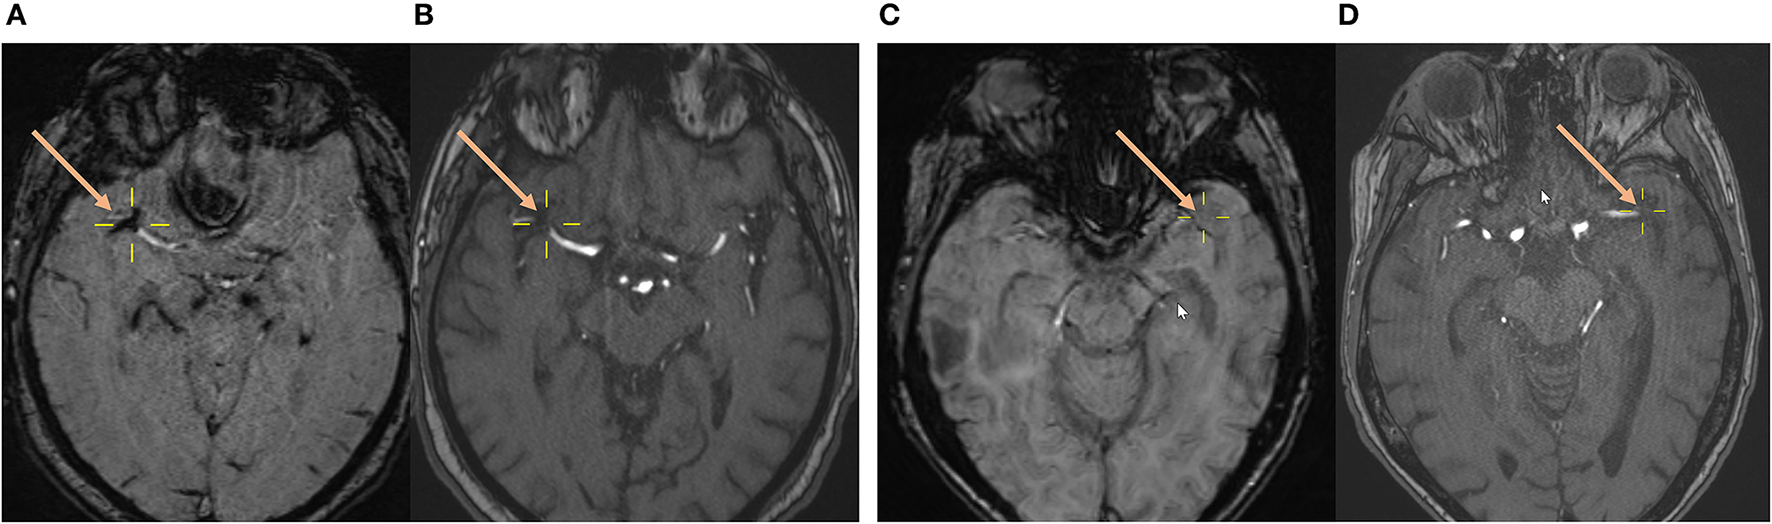

Imaging was performed on a 1.5 T or 3 T MR imaging scanner (1.5 T: Magnetom Avanto or Magnetom Aera; 3T: Magnetom Verio; Siemens). Magnetom Avanto 1.5 T SWI and 1.5 T Magnetom Aera SWI were performed with the following parameters: TR, 49 ms; TE, 40 ms; flip angle, 15.0°; section thickness, 1.6, 1.8, or 2.0 mm; and intersection gap, 0 mm. Magnetom Verio 3T SWI was performed with the following parameters: TR, 27 ms; TE, 20 ms; flip angle, 15.0°; section thickness, 2.0 mm; and intersection gap, 0 mm. The detailed method used to determine the presence of SVS in the cohort analyzed in this article was described by N. Belachew et al. in a previous publication (24). To summarize, SVS status was assessed retrospectively by two independent neuroradiologists (N.F.B. and E.B.A.). Both raters were blinded to clinical information and outcome, and were not involved in any patient treatment. Regardless of its diameter, SVS was determined to be present if a distinct signal loss corresponding to an occluded and symptomatic intracranial artery could be identified (Figures 1A,B), for which there was no alternative explanation (i.e., neighboring vein, petechial hemorrhage, or microcalcification in the neighboring parenchyma). If no such signal loss could be identified even though a symptomatic vessel occlusion was seen on angiography, SVS was determined to be absent (Figures 1C,D). Interrater reliability regarding SVS evaluation for the study cohort analyzed in this article has been assessed and published in a previous study showing very good correlation (Cohen's κ = 0.873, p < 0.001) (24).

Figure 1. Assessment of the susceptibility vessel sign status on baseline brain MRI. (A,B) A 74-year-old male patient with AIS and visible SVS as a circumscribed signal loss on the SWI (A) with complete occlusion of the right MCA (M1 segment) on arterial TOF (B). (C,D) A 77-year-old female patient with AIS and absent SVS on the SWI (C) despite complete occlusion of the left MCA (M1 segment) on arterial TOF (D). Yellow crosshairs and salmon arrows center, respectively, point to the proximal part of the vessel occlusion on SWI and TOF. AIS, acute ischemic stroke; MCA, middle cerebral artery; SVS, susceptibility vessel sign; SWI, susceptibility-weighted imaging; TOF, time-of-flight angiography.